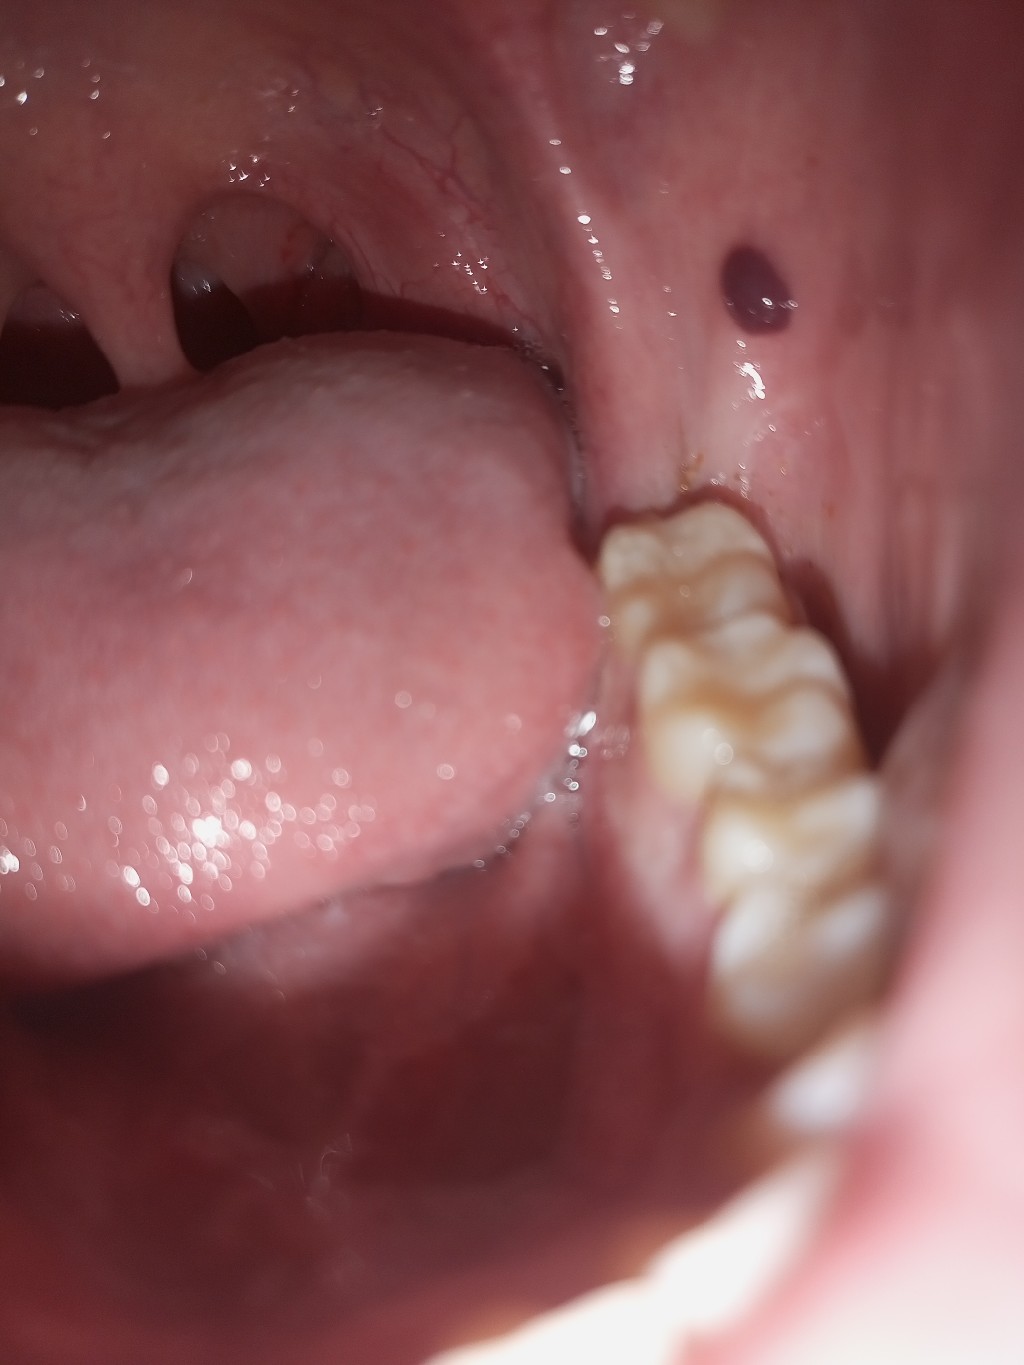

คืออะไรครับตุ่มเเดงๆเป็นตอนกินมะม่วงเสร็จ